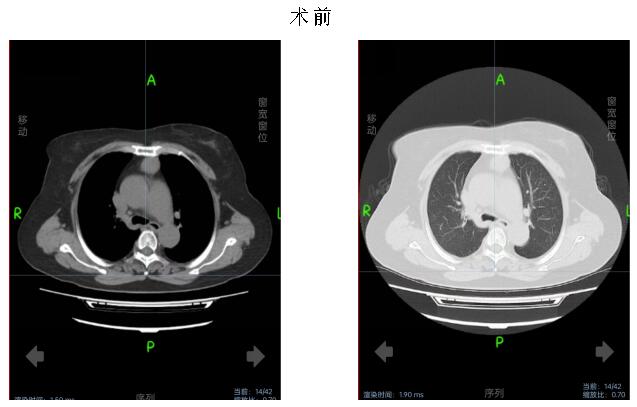

术中,在麻醉手术科配合下,李卫国带领胸外科团队为患者行胸腔镜经剑突肋缘三孔式胸腺病损切除术。术中送冰冻,30分钟后病理报告提示胸腺瘤,术后生命体征平稳,给予镇静止痛、营养支持等对症治疗。术后第3天复查胸部CT未见明显积液积气。患者无特殊不适。